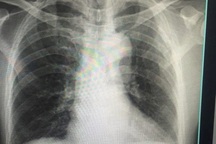

Câu được đưa đến Bệnh viện Việt Nam-Thụy Điển Uông Bí (Quảng Ninh) cấp cứu. Hình ảnh trên phim chụp X-quang cho thấy bệnh nhân bị gãy kín 1/3 dưới xương cánh tay phải. Bác sĩ chỉ định phẫu thuật nắn chỉnh xương và kết hợp xương nẹp vít.

Hình ảnh phim chụp X-quang của người bệnh trước phẫu thuật (bên trái) và sau phẫu thuật (bên phải).

Theo bác sĩ khoa Chấn thương - Chỉnh hình & Bỏng, Bệnh viện Việt Nam-Thụy Điển Uông Bí, bộc lộ ổ gãy 1/3 dưới xương cánh tay phải khi phẫu thuật các bác sĩ nhận thấy xương cánh tay bị gãy vặn xoắn đoạn chừng 8cm, di lệch nhiều, ổ gãy nhiều máu tụ. Ê kíp phẫu thuật đã tiến hành làm sạch ổ gãy, đặt lại xương và cố định lại xương cánh tay bằng nẹp, vít.